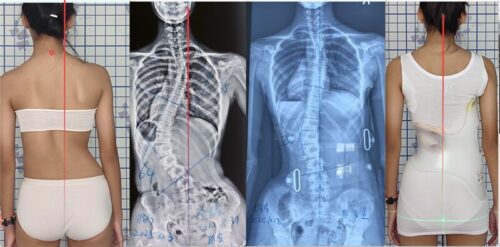

يُعدّ حزام اعوجاج العمود الفقري (Spinal Brace) أحد أكثر الوسائل غير الجراحية شيوعًا لعلاج الأطفال والمراهقين الذين يعانون من اعوجاج العمود الفقري (Scoliosis) خلال سنوات النمو. يعمل الحزام على تقويم العمود الفقري ومنع تفاقم الانحناء، ويُعدّ جزءًا أساسيًا من خطة العلاج للعديد من الحالات.

2. اعوجاج العمود الفقري الشديد أو المعقد

في بعض الحالات، يكون الانحناء شديدًا جدًا أو معقدًا (مثل S-shaped curves أو المنحنيات التي تتجاوز 45°)، ويحتاج الطفل لتدخل جراحي أو خطة علاجية متقدمة بدلاً من الحزام.

استخدام حزام اعوجاج العمود الفقري آمن وفعال لكثير من الأطفال والمراهقين، لكنه ليس مناسبًا للجميع. هناك علامات واضحة تمنع استخدامه، مثل الانحناءات الشديدة، مشاكل الجلد، اضطرابات التنفس، أو نهاية فترة النمو الحرجة.